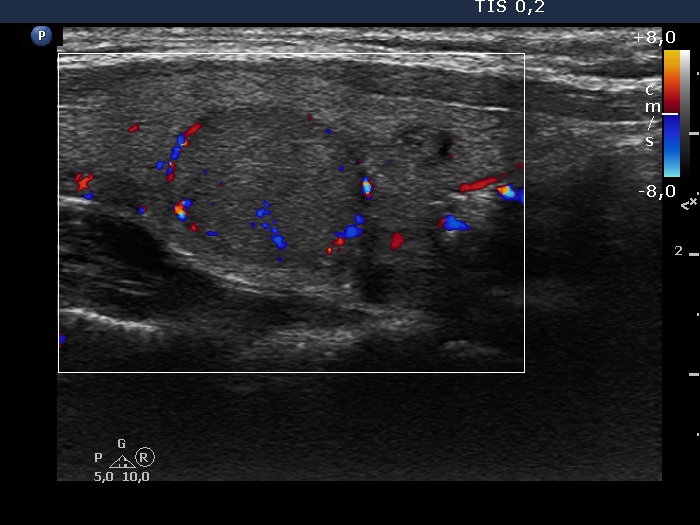

Right lobe, longitudinal scan

Left lobe, longitudinal scan, color Doppler mode. The lesion has perinodular vascularity.